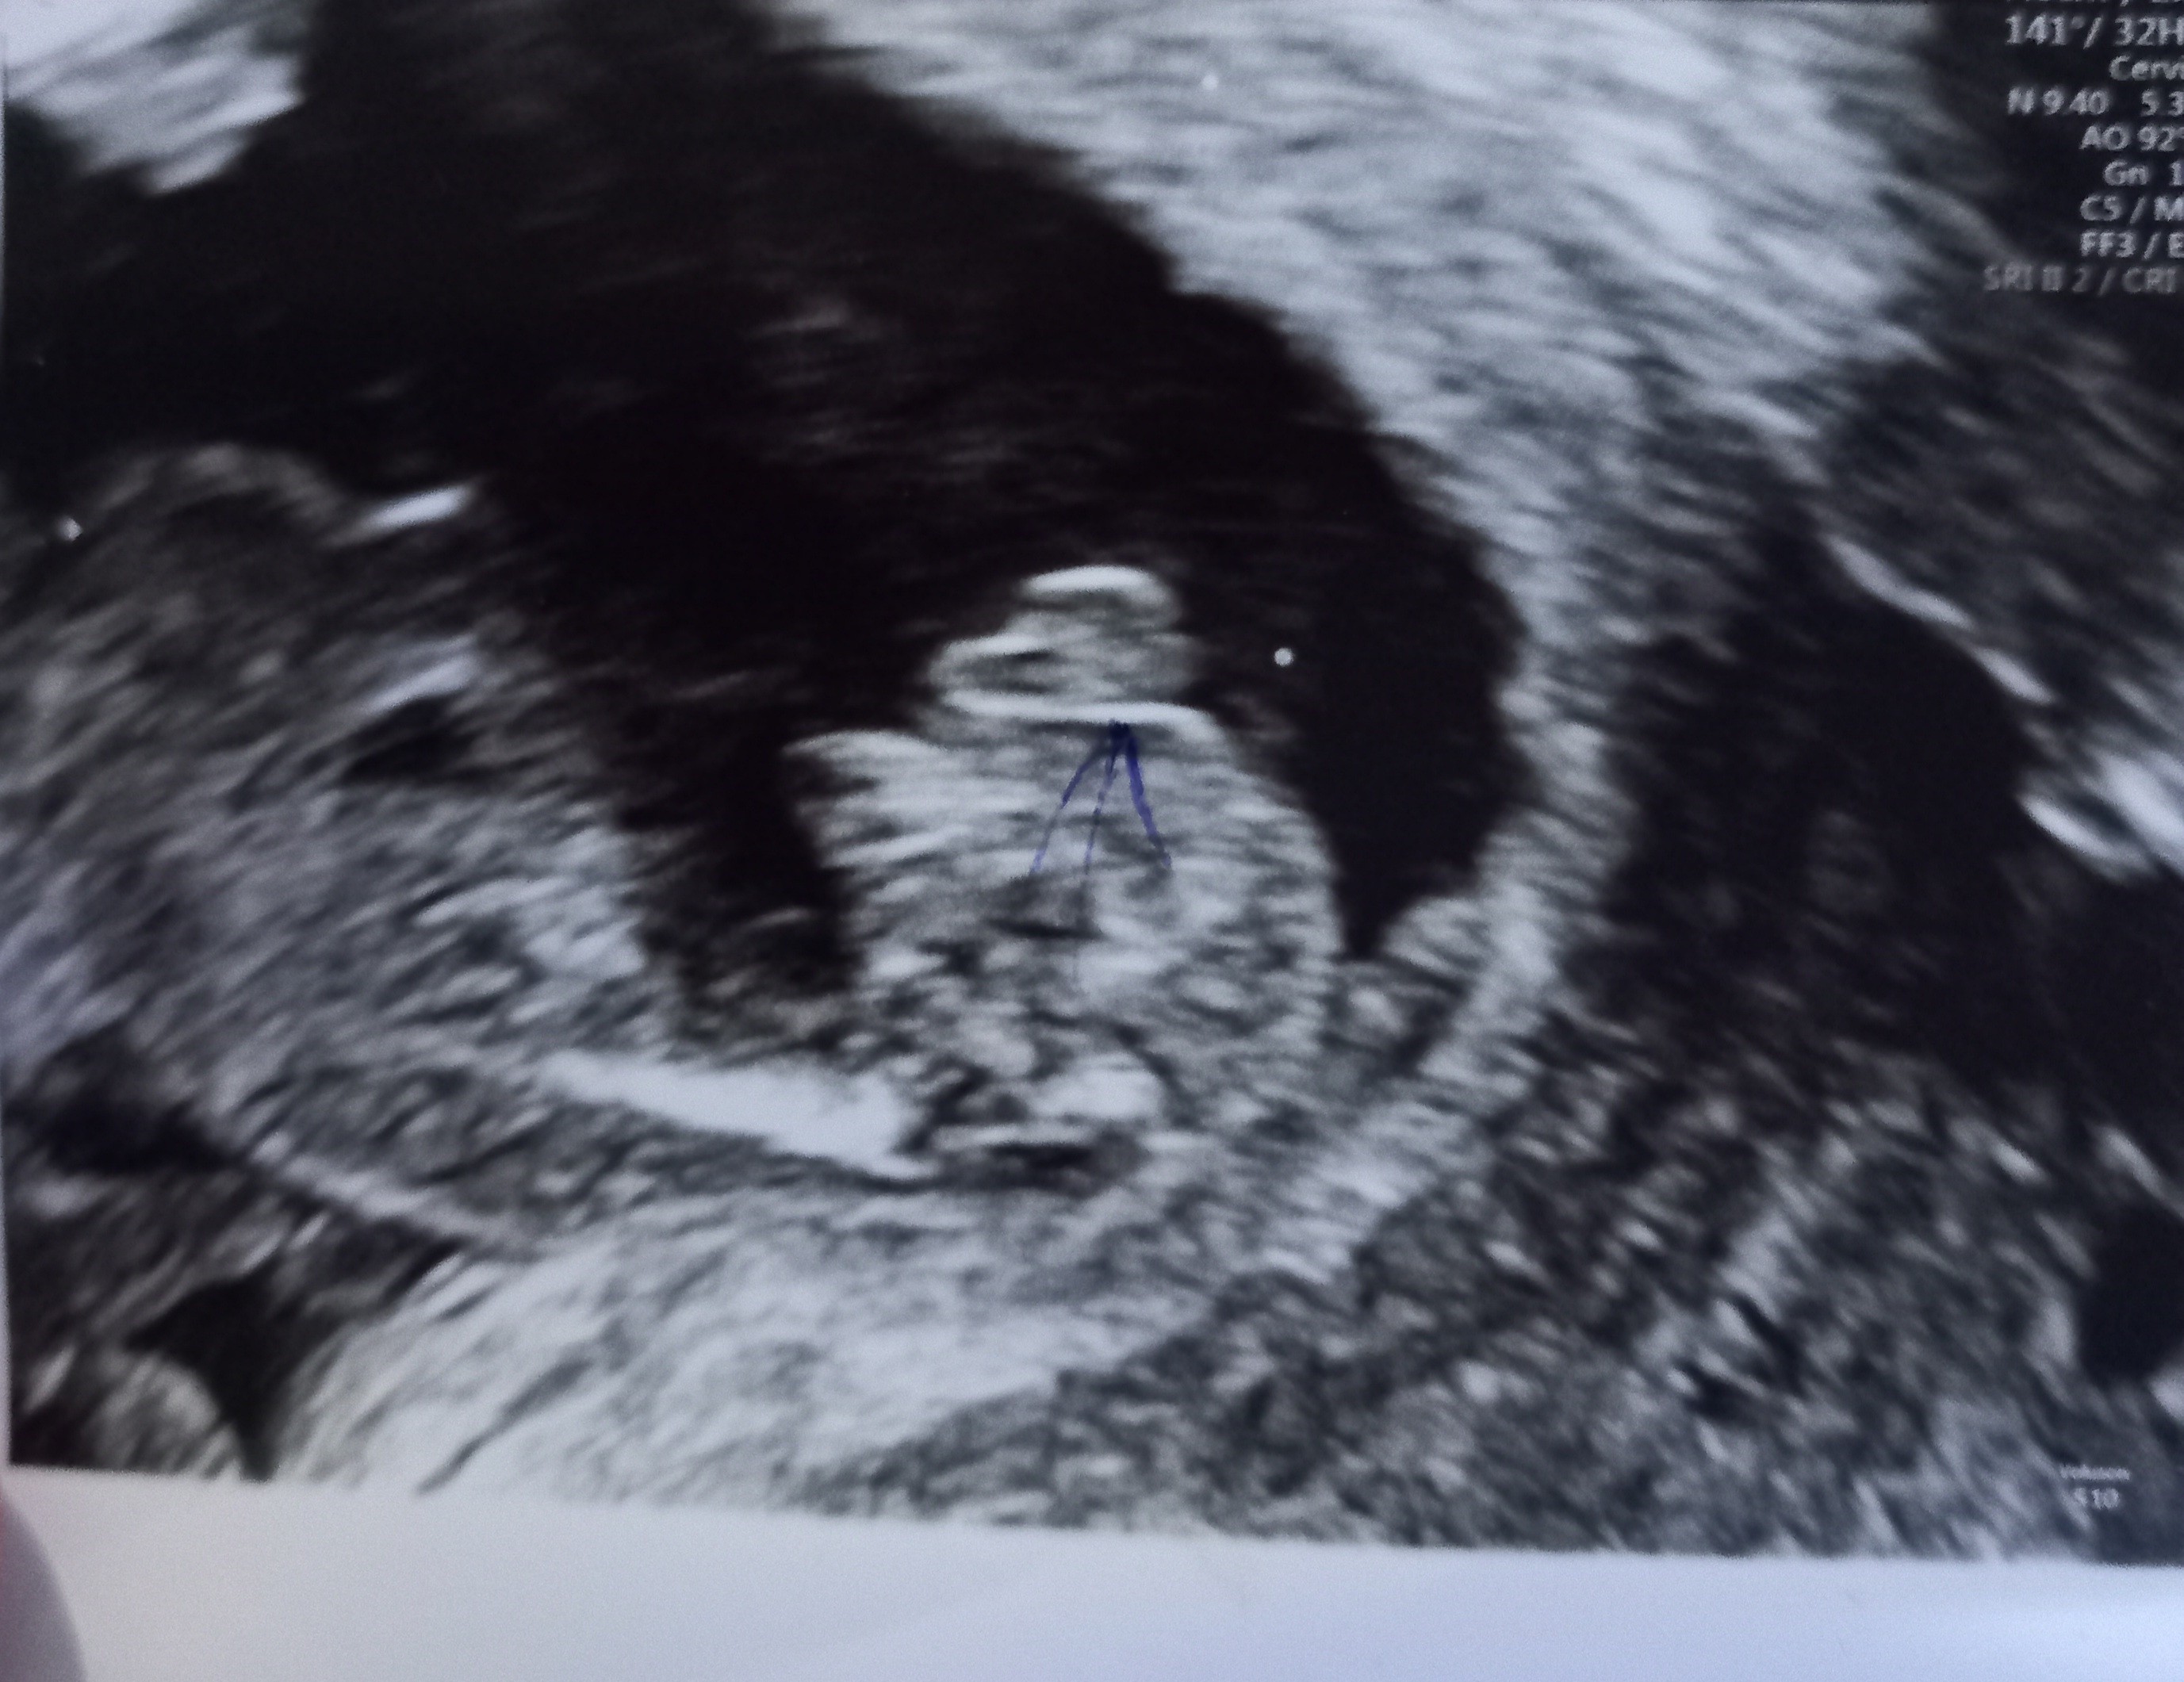

Jaką płeć dzidziusia widzicie?

Hej dziewczyny :) mam dokladnie takie samo pytanie.. usg z 18 tyg., jeszcze przed następna wizytą. Lekarz przewiduje dziewczynkę, a wy jak sądzicie?